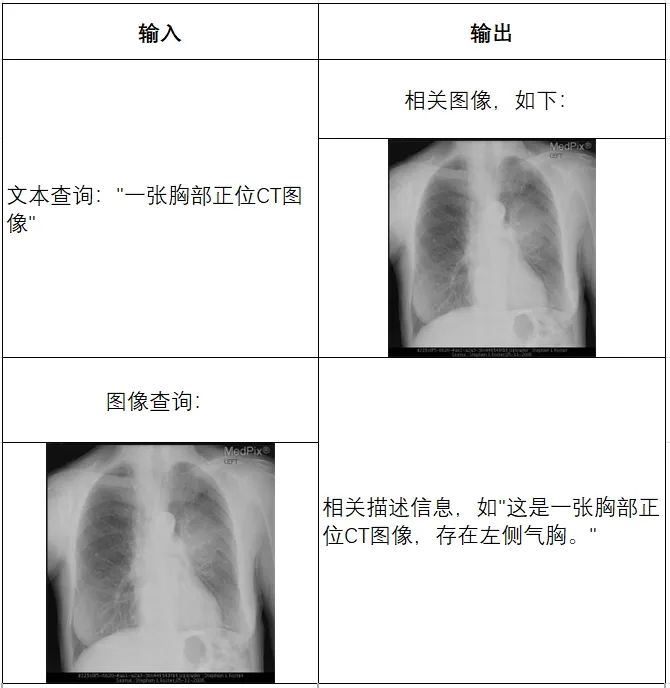

2.跨模态检索

支持跨模态查询,例如文本查询匹配图像,或图像查询匹配文本。例如当输入为文本时,如“一张胸部正位CT图像”,则会输出最相关的胸部CT的图片;而当输入为胸部CT的照片时,则会输出相关描述文本,如“这是一张胸部正位CT图像,存在左侧气胸”。